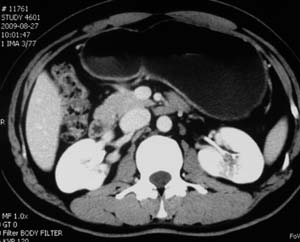

以下是引用子期在2010-3-19 20:47:00的发言:[br]血管畸形的ct增强应该有明显强化,本例并不相符合。本例双肾局部的略低密度影,累及肾盂,局部皮质明显变薄、内陷,增强扫描有轻度的强化,应考虑为炎性病变,患者为年轻男性,累及双肾的感染以结核较常见,可以没有明显的临床症状,尿中有时候也并不能查出什么;肾脓肿常有明显感染中毒症状,本例不符,另外一般的肾盂肾炎或肾小球肾炎通过小便就可确诊,其它还不能排除的是黄色肉芽肿性肾盂肾炎,然而单凭ct一般也很难鉴别。